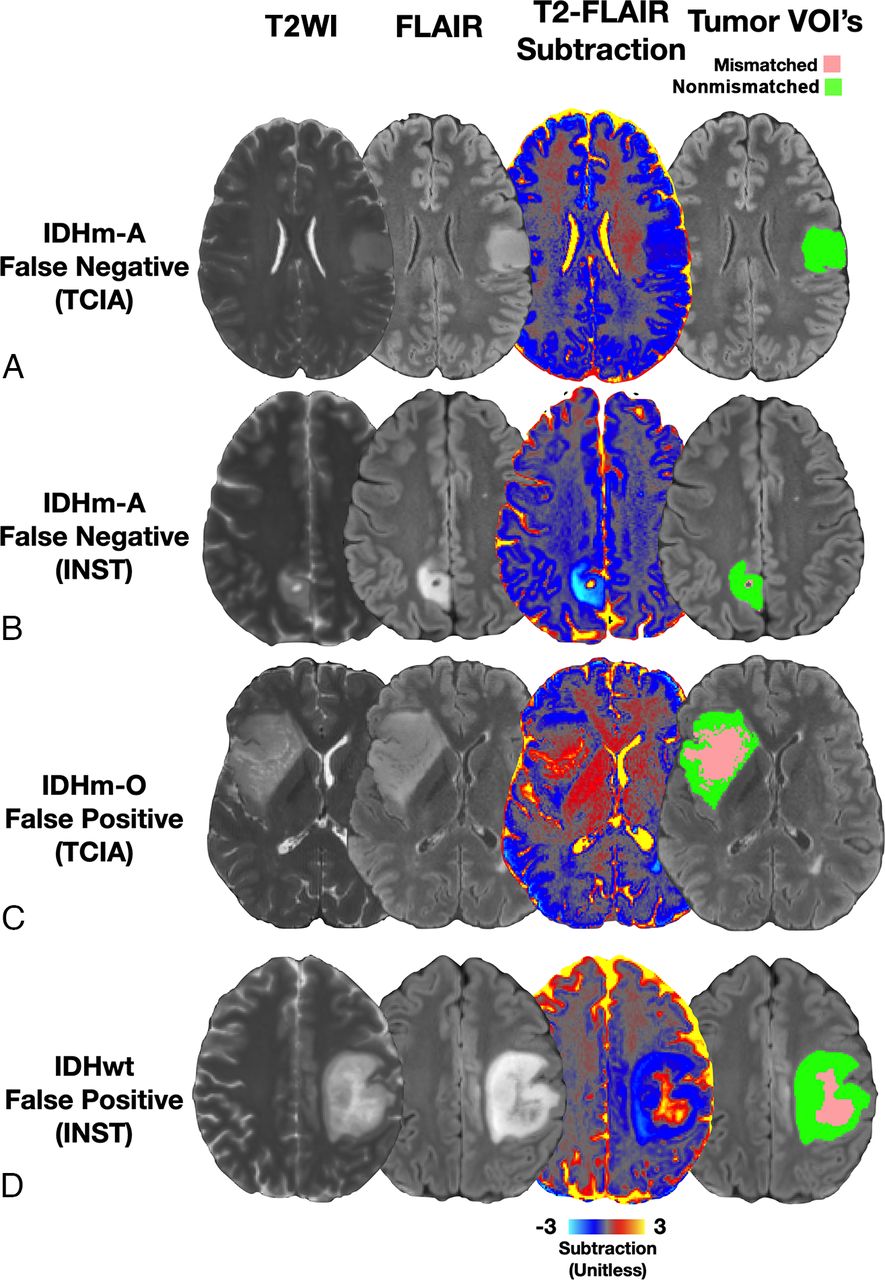

Eight representative cases across both cohorts are shown in Figs 1 and 2. Figure 1 displays typical true-positive and true-negative cases in the reader study. Patients 2A and 2B were diagnosed with IDHm-A, and T2-FLAIR subtraction maps clearly visualize T2FM subregions within these tumors and demonstrate 59.6% and 48.0% T2FM volume, respectively (Fig 1A -B, true-positive results). Patients 2C and 2D were diagnosed with IDHm-O and IDHwt glioblastomas, respectively, which demonstrate heterogeneous T2-weighted FLAIR hyperintensity, but T2-FLAIR subtraction maps demonstrated no corresponding T2FM subregions (Fig 1C, -D, true-negative results). Figure 2 demonstrates typical false-negative and atypical false-positive cases. Patients 3A and 3B were diagnosed with IDHm-A, but T2-FLAIR subtraction maps do not show T2FM subregions (Fig 2A, -B, false-negative results). Patients 3C and 3D were diagnosed with IDHm-O and IDHwt glioblastomas, respectively. These patients were interpreted as having the T2-FLAIR mismatch sign when using T2-FLAIR subtraction maps by at least one of the readers and demonstrated 35.0% and 12.5% T2FM volume, respectively (Fig 2C, -D, false-positive results).

Representative false-negative and false-positive cases with T2-FLAIR subtraction maps and tumor segmentations. A, Patient A is a 38-year-old man from the TCIA cohort diagnosed with grade 2 IDHm-A with no T2-FLAIR mismatch on the subtraction map (false-negative result). B, Patient B is a 36-year-old woman from the institutional cohort diagnosed with grade 2 IDHm-A with no T2-FLAIR mismatch on the subtraction map excluding the cystic portion (false-negative result). C, Patient C is a 45-year-old man from the TCIA cohort diagnosed with grade 2 IDHm-O demonstrating 35.0% T2FM volume, which was assessed as a false-positive for the T2FM sign by 1 reader using subtraction maps (false-positive result). D, Patient D is a 35-year-old woman diagnosed with IDHwt glioblastoma demonstrating 12.5% T2FM volume, which was assessed as a false-positive for the T2-FLAIR mismatch sign by both readers using subtraction maps. Corresponding tumor-segmentation VOIs of T2FM (pink) and T2FNM (green) subregions are shown (A–D) (false-positive result).